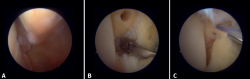

Evaluación artroscópica de la sindesmosis

Desde el portal anteromedial tenemos una visualización directa de las fibras distales del LTPA. Una desinserción de estas fibras no se traduce siempre en inestabilidad de la sindesmosis, pero nos obliga a comprobarlo. Los autores preferimos la evaluación del plano coronal de la sindesmosis. Introducimos el artroscopio en la articulación tibioastragalina dirigiendo la cámara hacia craneal. De este modo, tenemos una visión directa de la articulación tibioperonea distal. Entonces evaluamos la estabilidad intentando introducir el palpador en la articulación. Si es posible hacerlo, catalogamos la lesión de la sindesmosis como inestable (Figura 6A).

Evaluación artroscópica del ligamento deltoideo

Existen múltiples métodos para evaluar la inestabilidad del complejo medial; mediante los portales anteriores del tobillo es posible valorar la estabilidad del ligamento deltoideo en su plano principal de acción, correspondiente al plano coronal. Chun et al.(20) describió inestabilidad cuando es posible introducir un palpador artroscópico en el espacio medial tibioastragalino (Figura 6B). Vega et al.(21) describió que, en la mayoría de las lesiones, la porción más anterior del ligamento deltoideo está desprendida del maléolo medial, mientras que sus inserciones proximales permanecen íntegras. En esta situación se puede introducir el palpador artroscópico entre la pared medial del maléolo interno y las fibras profundas del deltoideo.

Técnica quirúrgica: tratamiento artroscópico de las lesiones agudas del complejo medial

En cuanto a la técnica quirúrgica, los portales de trabajo se realizarán de la misma manera que en una artroscopia de tobillo convencional: un portal anteromedial y uno anterolateral. Se inicia siempre con una artroscopia diagnóstica para confirmar la lesión del ligamento deltoideo. Puede utilizarse un palpador para verificar la laxitud de las fibras y realizar una prueba con este introduciéndolo a través de la gotera medial: si pasa, confirma la lesión. Para la reparación, el portal de visión será el anterolateral, así se trabajará de forma más directa a través del anteromedial. Las fibras anteriores del tibiotalar superficial e intermedias de la porción profunda del deltoideo son las que la técnica artroscópica permite reparar(38). Una vez identificado y disecado el ligamento, se pasa una sutura entre las fibras mediante un pasador de sutura. Se prepara la zona de anclaje del maléolo medial con un rasurador o una pequeña fresa. Con el tobillo en posición neutra se introduce el ancla manteniendo la tensión de las suturas. Se puede utilizar como referencia anatómica para la colocación la intersección de la línea paralela a la articulación tibiotalar y una línea perpendicular marcada desde la punta del maléolo y por el borde lateral de este(21). Tras realizar la reducción, se prueba nuevamente la tensión de las fibras y el paso del probador por la gotera medial, que confirma una adecuada reparación (Figura 8).

Figura 5. A: visión anterior del receso medial del tobillo; B: con el palpador tensamos las fibras del ligamento tibiotalar profundo.

Figura 6. Maniobras para evidenciar inestabilidad ligamentosa. A: lesión de la sindesmosis que permite la introducción del palpador en la tibioperonea distal; B: lesión del deltoideo que permite la introducción del palpador en el espacio medial tibioastragalino.